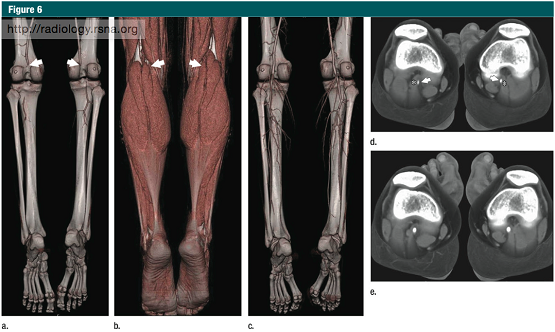

下肢CT血管造影(与磁共振血管造影)因为其广泛的适应症(38),最重要的是指导外周动脉疾病患者的治疗计划& #40;44& #41;,事实上已经取代了诊断性动脉内造影。其他适应症还包括急性下肢动脉缺血,创伤及解剖成像,如之前的游离皮瓣移植术(45),或疑有功能性或解剖性的运动员腘动脉受压综合征(图6)及髂动脉内纤维化(38)。 Lower-extremity CT angiography & #40;and MR angiography& #41; has virtually replaced diagnostic intra-arterial angiography for abroad spectrum of indications & #40;38& #41;, the most important of which is treatment planning for patients with peripheral artery disease & #40;44& #41;. Other indications include acute ischemia, trauma, andanatomic imaging, such as before free-flap harvesting & #40;45& #41;, or inathletes suspected of having functional or anatomic popliteal entrapmentsyndrome & #40;Fig 6& #41;, or iliac endofibrosis & #40;38& #41;.

图6 :19岁,篮球运动员,在球场上跑步的时候腿部出现疼痛 CT血管造影诊断为腘动脉受压综合征 (a)跖屈应力体位(负荷状态),VR图像显示,双侧腘动脉闭塞(箭头所示),同时小腿远段动脉几乎没有显示。(b)VR使用相同的数据、运用多层次交互显示方法显示下肢肌肉,腘动脉闭塞的位置(箭头所示)相当于腓肠肌内侧头部的水平,和图a相同(c)VR-CT血管造影示静息状态下、中立位,腘动脉和小腿动脉的正常图像。(d)负荷状态下,腓肠肌内侧头部水平的双侧异常腘动脉(箭头所示)(e)静息状态下,腓肠肌内侧头部水平的双侧腘动脉